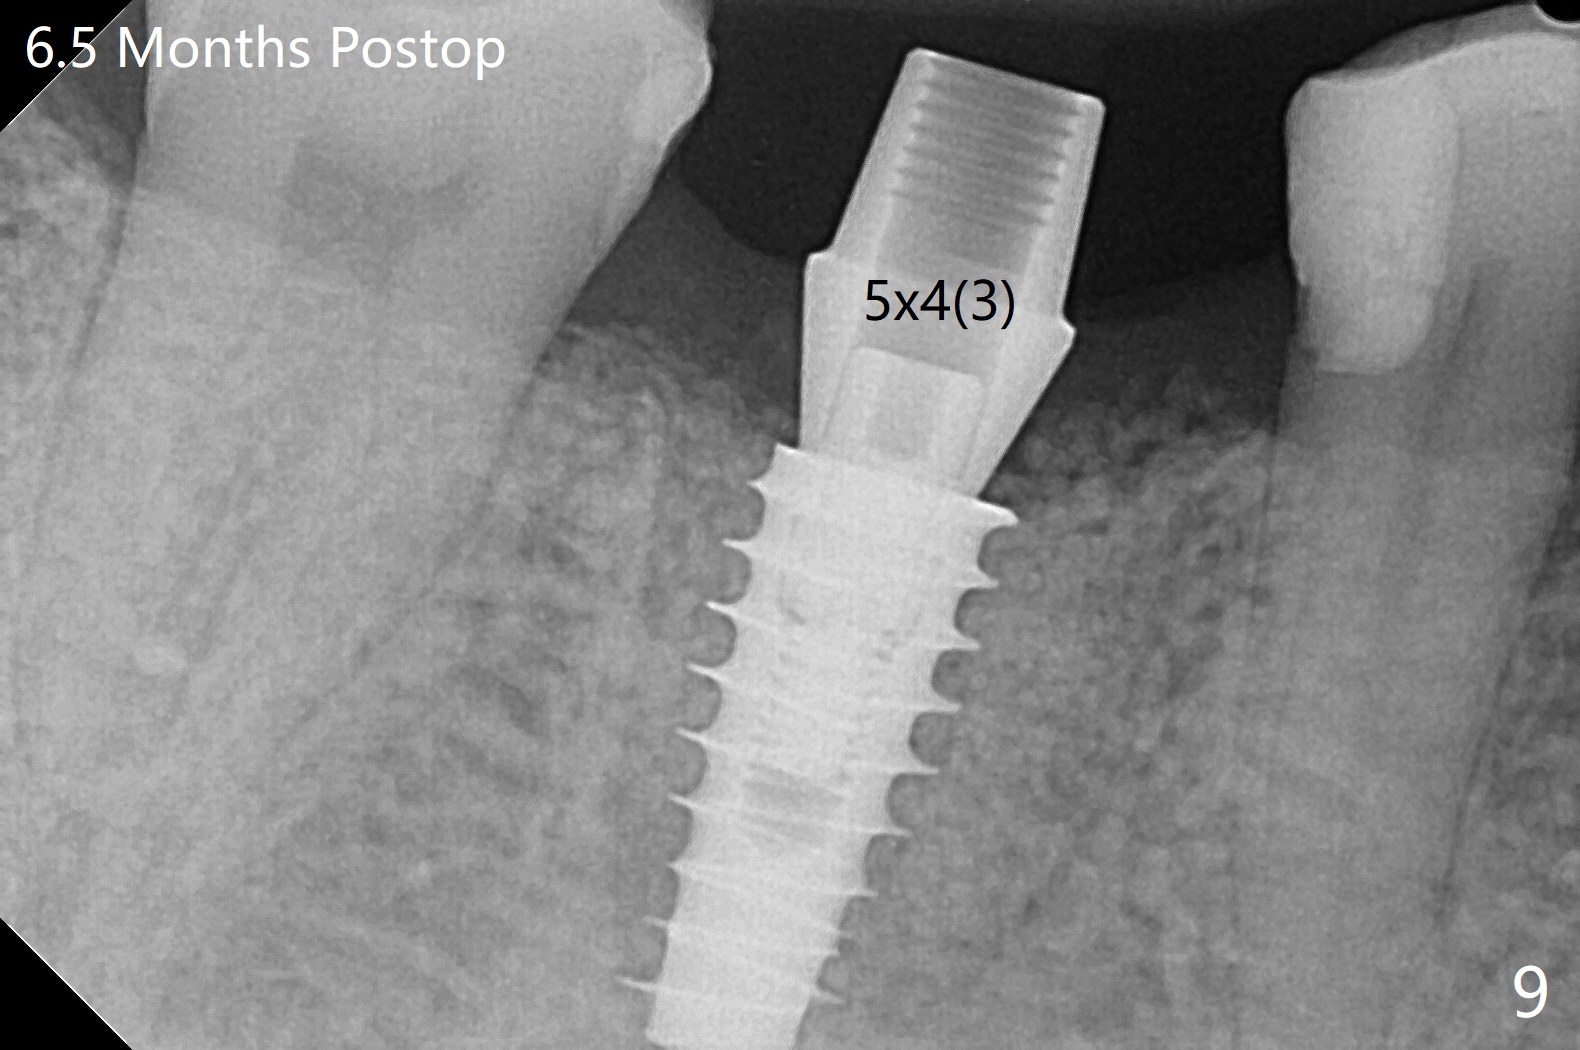

牙冠断裂,好像容易保留牙根,其实还挺多工作。使用12毫米平磨钻头后,中隔中央形成凹陷,不过使用2.2x7.3毫米钻头后,钻洞开始偏移远中(图一)。完成3.5x11.5毫米钻洞,4x10毫米报废植体扭力很高(图二)。为了植入5x11毫米植体(扭力35Ncm),必须使用4.5x11.5毫米钻头(图三)。虽然根尖骨质不多,稳定性部分来自残余颊侧,舌侧中隔。即刻放置的基台远中舌侧必须大量磨去(图四:^)才有足够空间做临时牙冠,说明牙冠会折裂病人咬合力大。保留牙根工作量大,仍有偏差(与图五(设计)相比),仿佛好处不大,以后少做。由于临时牙冠舌侧做的大些,术后八天取出修正,伤口愈合正常(图六)。术后一个月一部分骨粉好像被转化为牙龈(图七)。术后3.5月病人抱怨咀嚼疼痛,植体松动,放置愈合基台。一个月后植体仍松动,疼痛(图八)。术后6.5月,植体不再松动,放置修复基台(图九),取模。